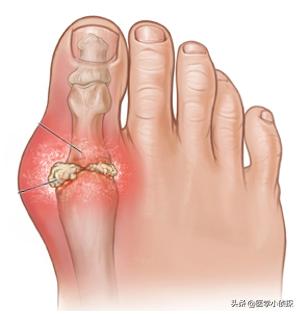

関節の周囲や耳介に痛風結節があり、長期にわたる痛風の場合、関節は萎縮し、変形し、しばしば潰瘍化し、傷口からカルキ状の分泌物が出る。

そして、この部分の皮膚の中で痛風結石が成長する進行痛風と、骨の上で成長する小さな硬い結節であるリウマチ結節の違いがある。

痛風結石はほとんどすべての痛風患者の体に見られ、病気が進行するにつれて蓄積していく。は手足の関節を破壊し、慢性的な関節の腫れや痛み、こわばりや変形、さらには骨折を引き起こす。

痛風結石の発見

皮下の痛風結石の典型的な部位は耳介で、反回関節周囲、タカサゴ、アキレス腱、膝蓋囊などが一般的である。外観は皮下に大小さまざまな黄白色の赤色を帯びた菌が隆起し、皮膚表面は薄く、破れると白い粉状またはペースト状のものが排出され、長期にわたって治癒しない。皮下痛風結石はしばしば慢性痛風結石性関節炎と併発する。痛風結石が関節に大量に沈着すると、関節骨の破壊、関節周囲組織の線維化、二次的な退行性変化を起こすことがある。